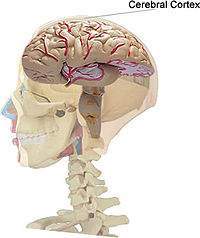

Corteza cerebral

Encéfalo: Corteza cerebral | |

Corteza cerebral. La corteza de los hemisferios cerebrales es la sección más alta del sistema nervioso central, el último en desarrollo, y el más complicado en estructura y función.

Los elementos estructurales de la corteza son células nerviosas que emiten procesos, axones y dendritas, y las células de la neuroglia. La corteza cubre toda la superficie de los hemisferios cerebrales; varía en grosor desde 1,5mm hasta 3mm. Su área total en ambos hemisferios en el hombre es entre 1450 y 1700 cm2. Contiene entre 12 y 18 mil millones de neuronas. Una peculiariedad de su estructura es la distribución de las células nerviosas en varias capas una sobre la otra. Las capas son distinguidas por los aspectos siguientes.